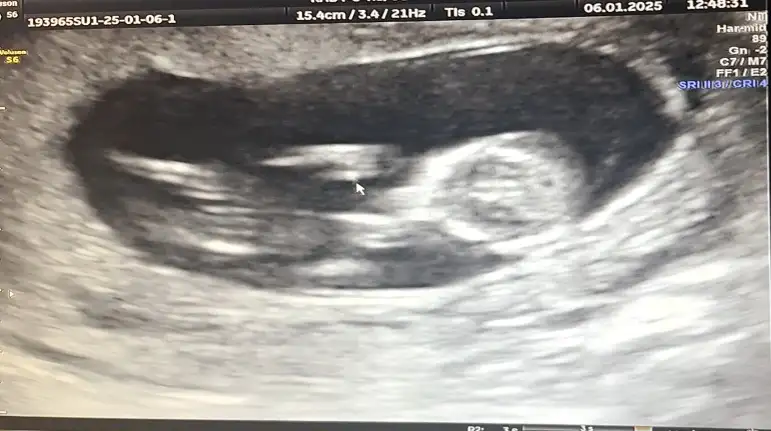

Hanımlar selam 13+2 den selam kontrolden çıktım şimdi.

Cinsiyet tahmini olan var mı? 🤣🤣🤭🤭🤭🤭